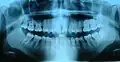

Ортопантомограмма зубов

Рентгенограмма (слева-направо) третьего, второго и первого коренных зубов в различных стадиях развития

Рентгенограмма нижнего правого третьего, второго и первого моляров на разных стадиях развития